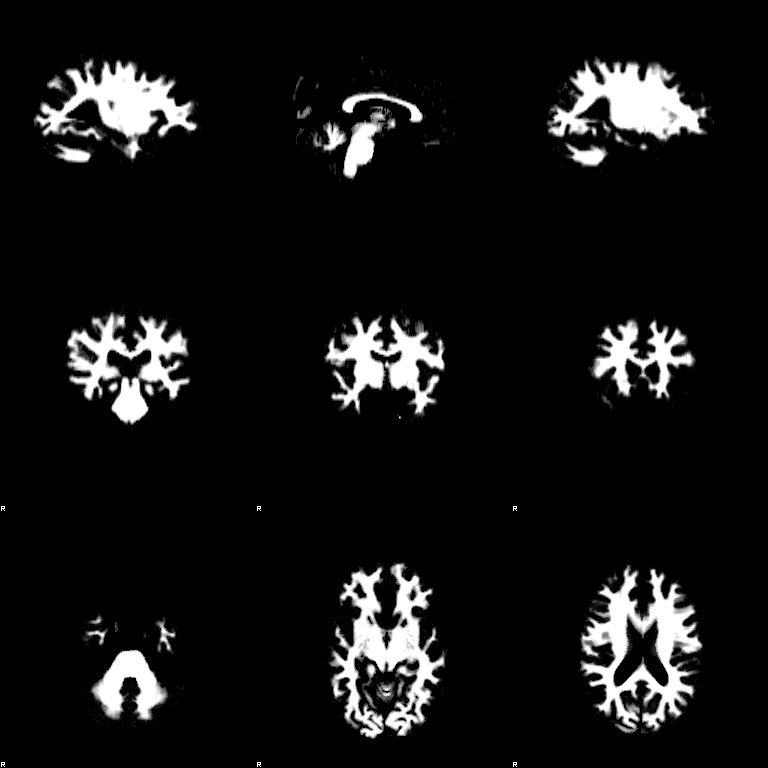

FAST

Set the Input image to be structural_brain (i.e. it is important to have run BET first). Turn on the Partial volume maps optional output images. Press Go. The outputs will be structural_brain_seg, structural_brain_pve_0, structural_brain_pve_1 and structural_brain_pve_2.